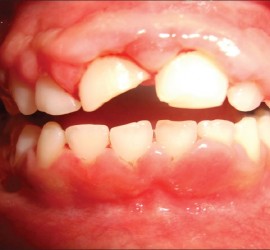

Аномалии строения и пороки развития зубов Пороки тканей зуба многообразны, они могут проявляться изолированно и сочетаться с аномалиями строения и пороками развития органов и систем всего детского организма, в том числе челюстно-лицевой области. Ткани зуба имеют эктодермальное (эмаль) и мезодермальное (дентин, пульпа, цемент) происхождение. В связи с этим пороки эмали […]